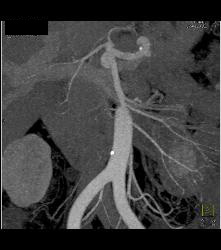

Lower Pole Right Renal Cell Carcinoma With Cystic Pancreatic Lesion in Von Hippel-Lindau syndrome (VHL) - See Sequence